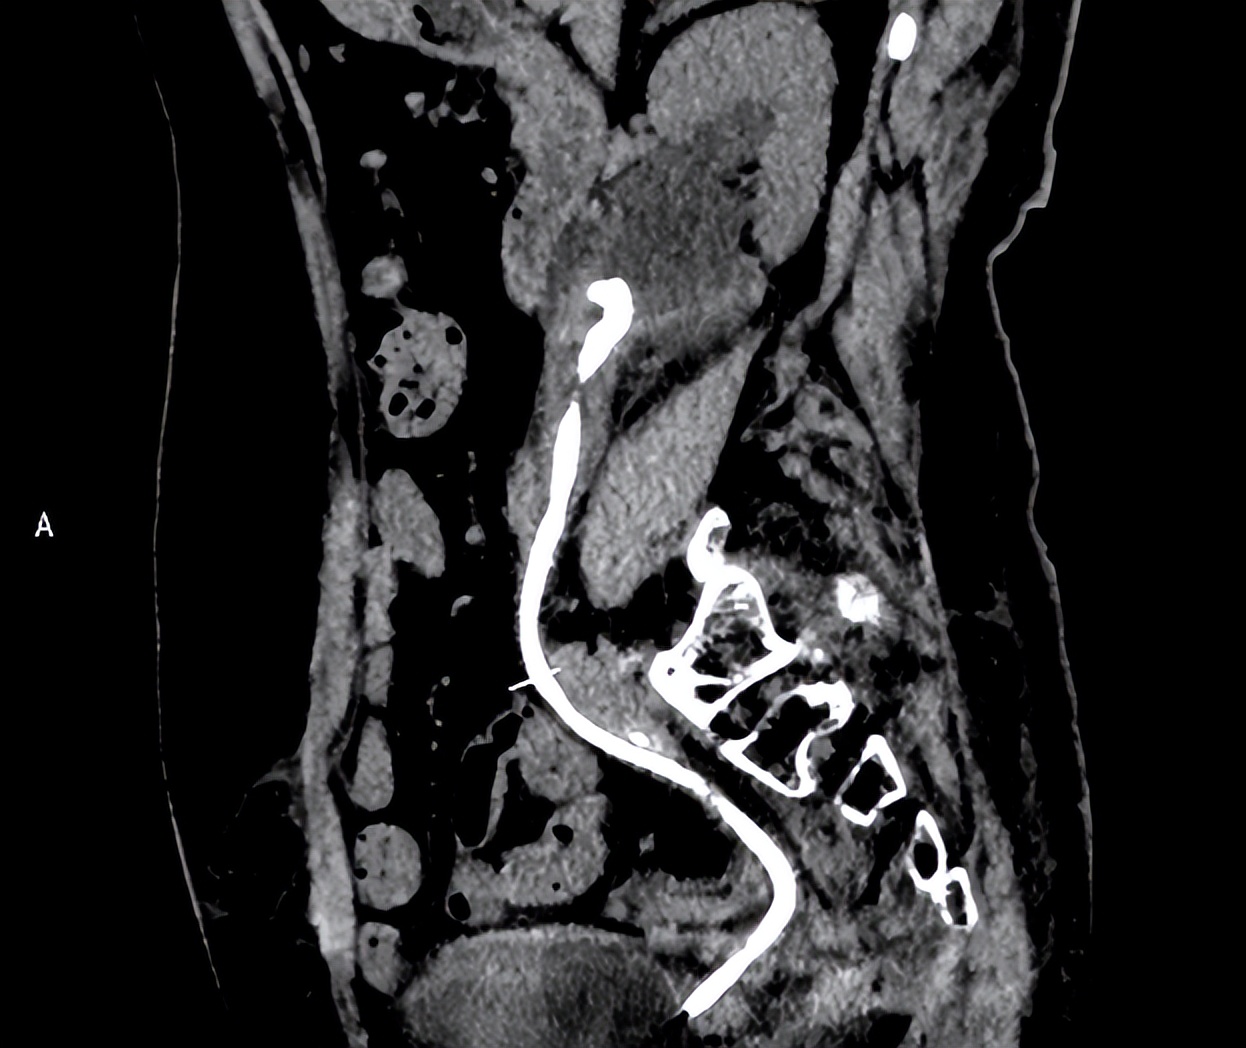

患者的三维CT重建图

凭借丰富的临床经验,任明华教授指出正常输尿管支架管直径不会这么宽,推断患者体内的输尿管支架管表面覆盖一层结石,结石可能嵌顿在输尿管内。